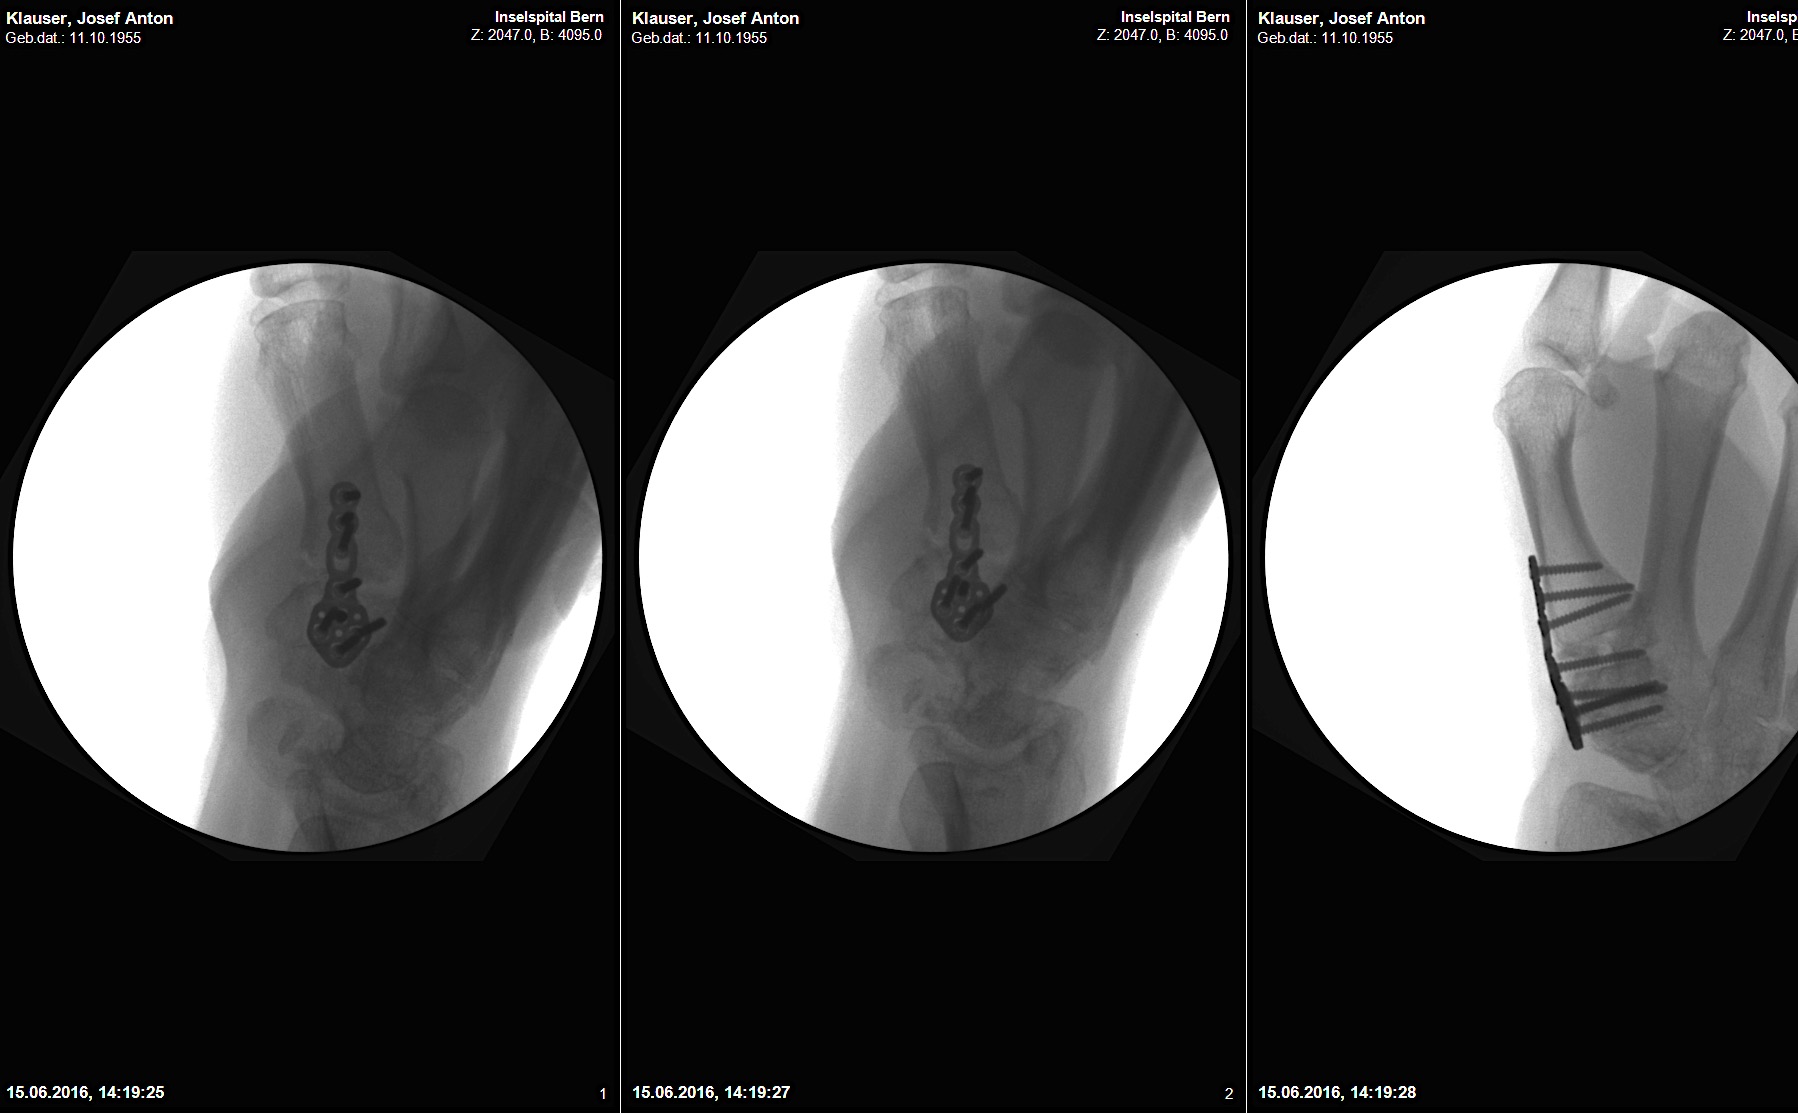

Case 1:

A 64-year-old male suffered a multi-fragmentary fracture of his right thumb metacarpal (Fig 1). An adapted 12-hole strut plate from the variable angle locking hand system was the implant of choice for fixation (Figs 2 - 4).

The strut plate provided good stability in a comminuted extraaricular fracture pattern and enables immediate mobilization. Bone callus formation was not witnessed during the healing process.